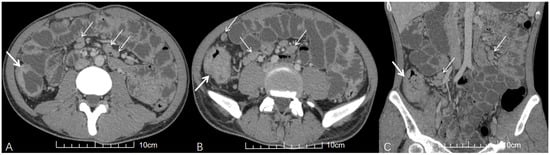

3.3. CT Characteristics of ATBL

4.3. CT Imaging Analysis